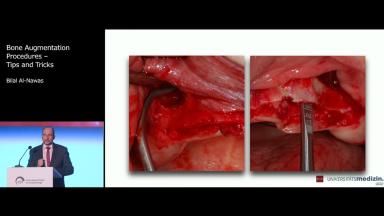

Bone Augmentation Procedures – Tips and Tricks

This lecture deals with different types of bone defects and discusses how those defects might be reconstructed. Indications for use of bone substitutes and different types of barrier membranes are also presented. Particular attention is paid to the reconstruction of extrabony defects by means of the bone split technique, sandwich osteoplasty or use of block grafts. Application of custom-fabricated CAD/CAM mesh and different types of incisions and flaps for bone reconstruction are also presented. Finally, the most common complications in bone reconstruction and their etiology are discussed.